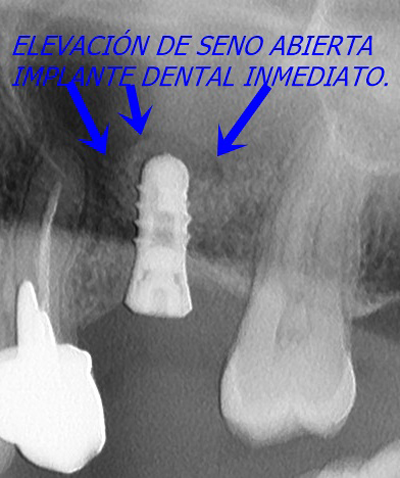

Decidimos realizar una elevación de seno abierta en la que a través de una ventana quirúrgica, despegamos la membrana del seno para al mismo tiempo rellenar con hueso, en este caso gránulos óseos con colágeno de origen natural, el espacio necesario para colocar en el mismo acto un implante dental de alta gama. Posteriormente utilizamos una membrana de colágeno para tapar ventana que hemos creado.

Gracias a esta técnica conjunta de elevación abierta y colocación de implante conseguimos no solamente ahorrar varios meses de espera al paciente sino, sobre todo, el tener que realizar una segunda intervención quirúrgica. Sólo tendremos que esperar entre 3 y 4 meses para que los implantes se integren bien en el hueso y podamos tomar los moldes con los que confeccionar una funda dental hecha a la medida.